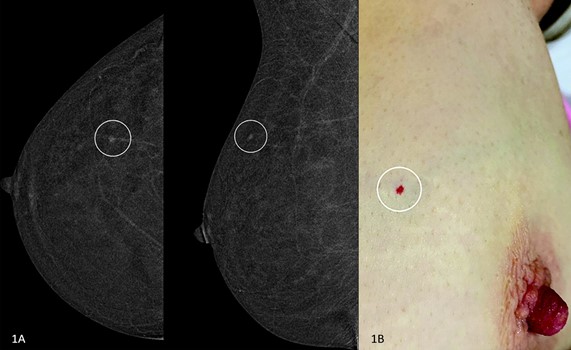

Drs. Berg, Patel, and myself will provide a case-based introduction to the most common artifacts and cancer mimics on CEM, too. This topic is continuously evolving. In the July issue of AJR, enhancing cherry hemangioma has been described as a common benign finding that may be misleading (Fig. 2) [5]. It is helpful for the technologist to make note of skin lesions, which can be marked to facilitate recognition.